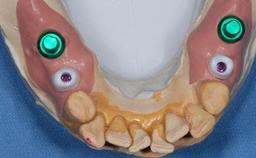

The patient presented with a failing tooth-supported fixed dental prosthesis with cantilever extension replacing the right maxillary central incisor. His chief presenting complaint was poor esthetics, in particular the dark discolored margin around the abutment tooth, the maxillary left central incisor. He reported a history of trauma at a young age, which necessitated the replacement of his maxillary right central incisor as well as root canal therapy of the adjacent left central incisor. The existing prosthesis had been in situ for over 20 years. The initial periapical radiograph displayed good proximal bone levels at the adjacent teeth and a wide incisive canal, which was a concern. The left central incisor presented a very wide root canal treatment with compromised radicular dentin thickness, which was a consideration in the decision between a new tooth-supported fixed dental prosthesis vs. an implant-supported prosthesis. After a lengthy discussion on the risks and benefits of both treatment options, the patient decided on a single-tooth implant replacement.